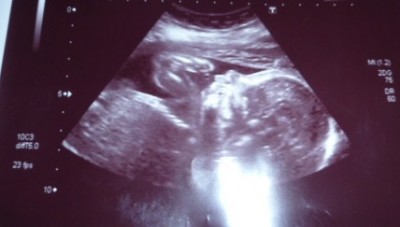

ich bin soooooooo glücklich unser Maus bleibt ein Mädchen und ist 26cm un 414g leicht!

Jaqueline, gratulation zum Mädel

tolle Bilder